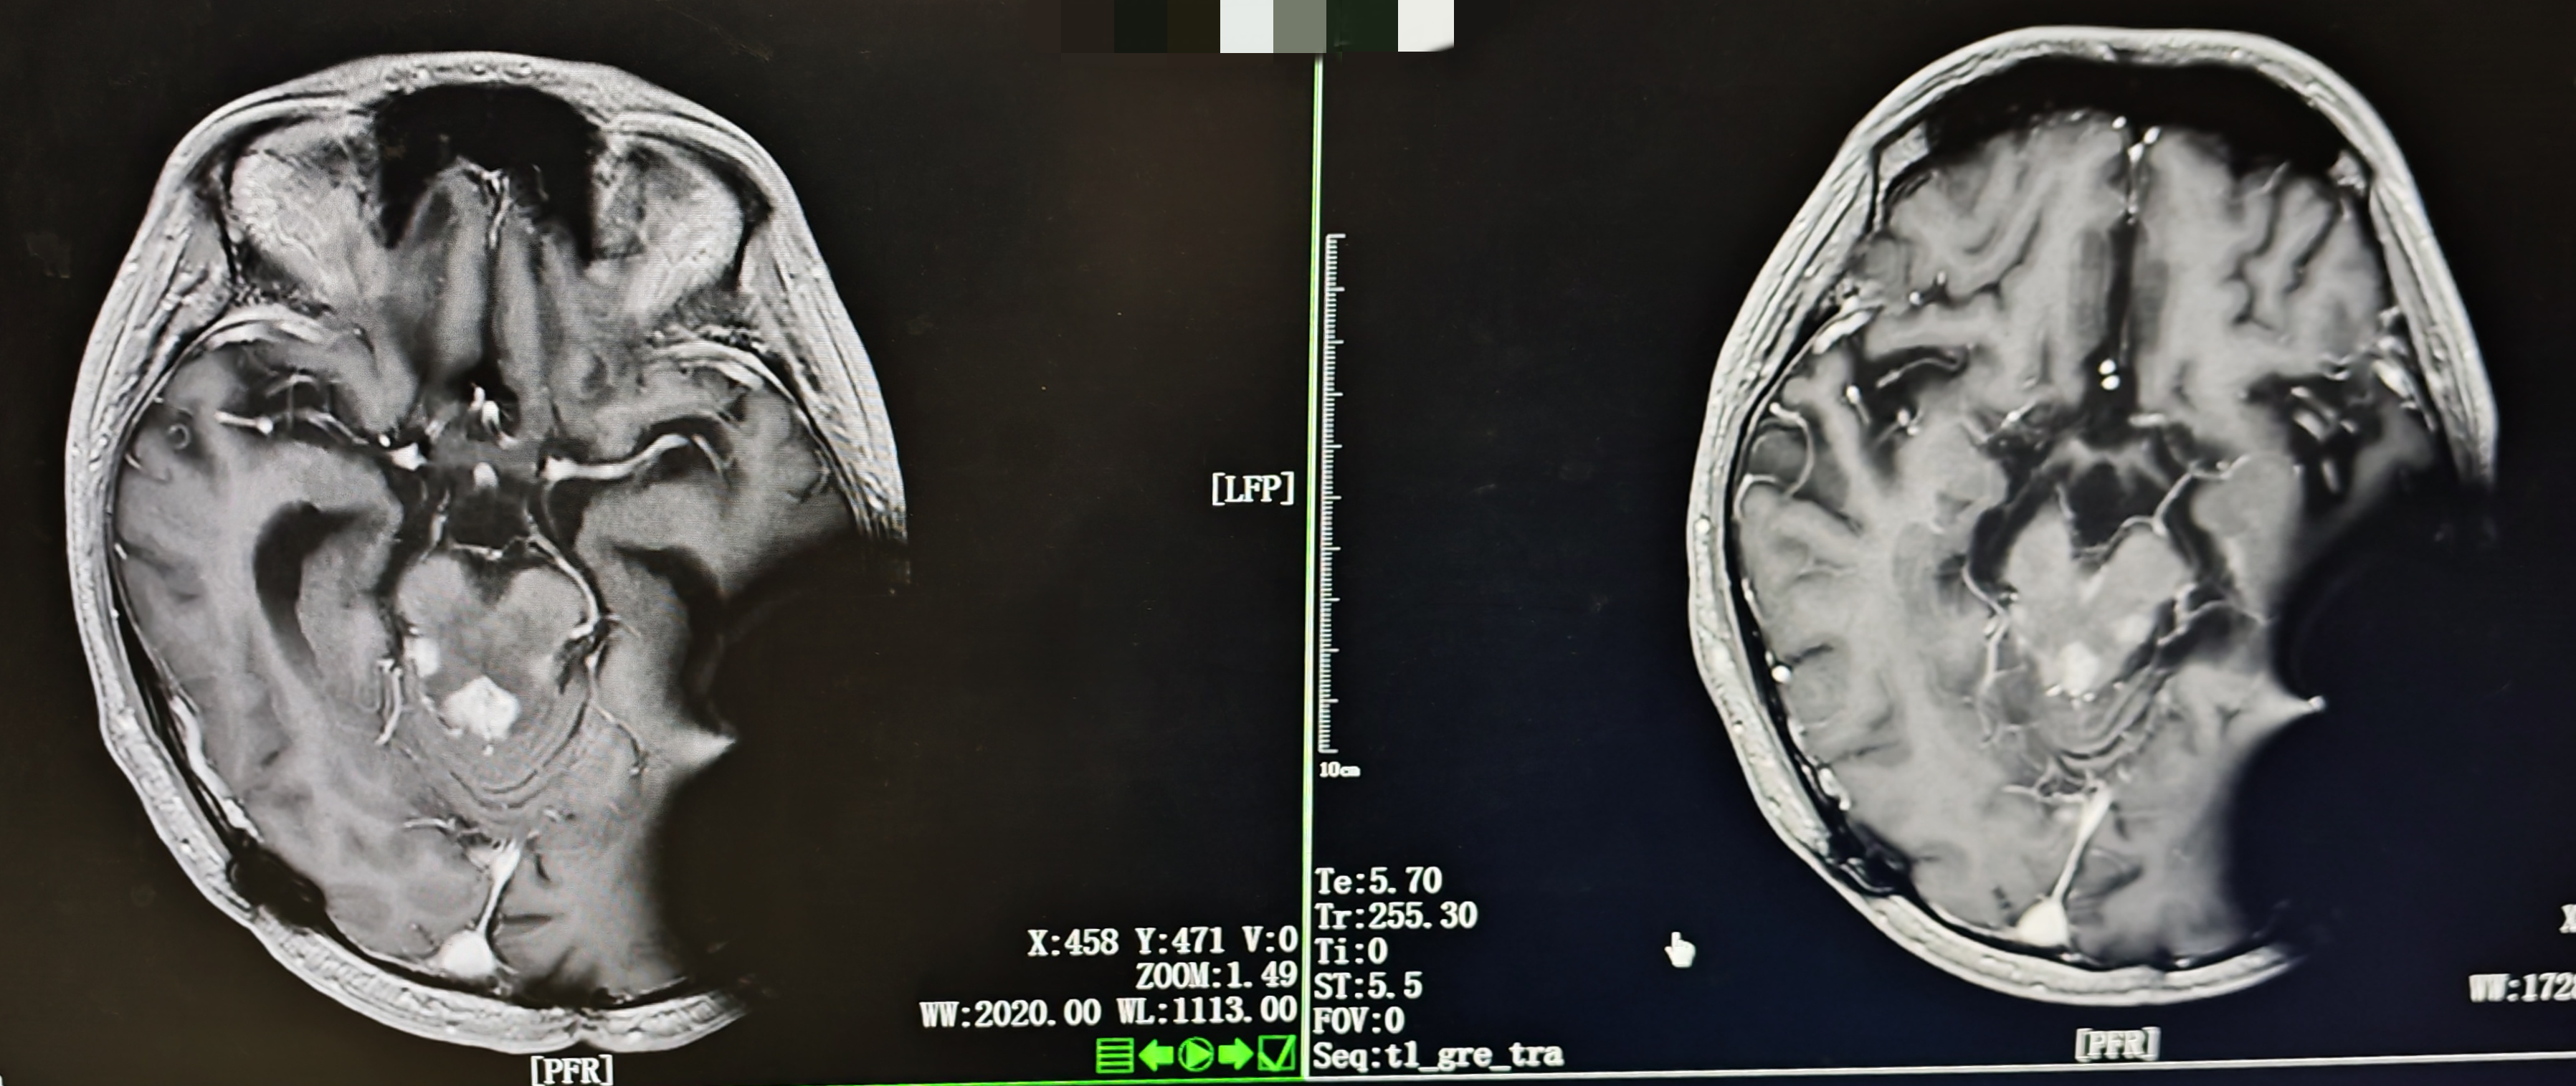

• 影像学(2025-08-06):头颅MRI示脑干及双侧丘脑病灶较前缩小,幕上脑室轻度扩张。

图 头颅MRI(左:2025年7月17日;右:2025年8月6日)

[2025-07-18] ➤ 第1周期化疗方案:贝伐珠单抗(100mg d1) + 去水卫矛醇(40mg d4-6) + 洛莫司汀(80mg d7);化疗后复查MRI示病灶较前明显缩小。

• 创新性采用"贝伐珠单抗+去水卫矛醇+洛莫司汀"联合方案,治疗后病灶显著缩小。